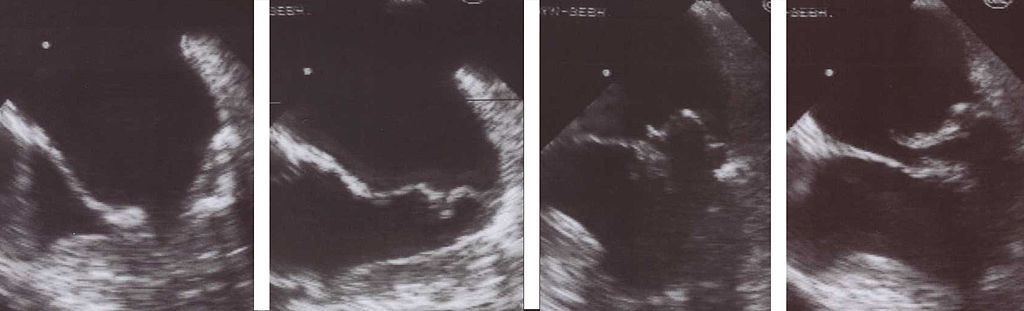

Mitral Stenosis

The narrowing of the mitral valve orifice is known as mitral stenosis.

Mitral stenosis is associated with persistent rheumatic valve disease.

Clinical findings of mitral stenosis include:

- An opening snap followed by a diastolic rumbling

- Volume overload that causes the left atrium to enlarge

- Pulmonary congestion with edema and alveolar hemorrhage

- Pulmonary hypertension

- Possibly right-sided heart failure

Mitral stenosis may cause atrial fibrillation with associated risk for mural thrombi.